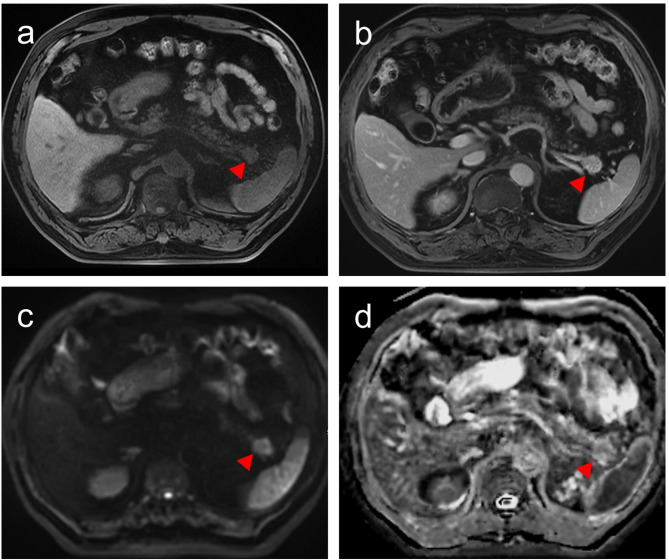

目的:准确预测小胰腺导管腺癌(sPDAC)(≤2 cm)隐匿淋巴结转移(OLNM)对治疗至关重要。本研究旨在探讨sPDAC中与OLNM相关的临床和MRI特征及其病理和预后意义。材料和方法:本回顾性研究纳入了2014年9月至2023年9月间接受手术的135例病理证实的sPDAC患者。分析术前多序列MRI、临床资料及病理特征。采用单因素和多因素logistic回归模型确定sPDAC患者发生OLNM的风险预测因素。采用受试者工作特征(ROC)分析评估诊断表现,采用Kaplan-Meier生存分析评估预后结果。结果:43例(31.9%)sPDAC患者存在OLNM。单因素和多因素分析表明,CA19-9升高(100 U/mL) (OR = 2.404, P = 0.040)和低表观扩散系数(ADC)值(OR = 0.243, P = 0.031)是OLNM的独立预测因子。临床-放射联合模型的AUC为0.740,显著高于CA19-9 (AUC = 0.653, P = 0.021)或ADC单独(AUC = 0.635, P = 0.035)。sPDAC合并OLNM患者淋巴血管浸润率(44.2%,P = 0.013)和病理性脂肪浸润率(86.0%,P = 0.030)较高。OLNM与较差的OS和DFS相关(P = 0.034和0.043)。结论:OLNM具有不良病理特征和较差的预后。术前MRI评估ADC和CA19-9可能有助于识别有OLNM高风险的sPDAC患者。临床试验号:不适用。

Results: OLNM was present in 43 (31.9%) sPDAC patients. Univariate and multivariate analysis identified elevated CA19-9 (> 100 U/mL) (OR = 2.404, P = 0.040) and low apparent diffusion coefficient (ADC) values (OR = 0.243, P = 0.031) as independent predictors of OLNM. The combined clinical-radiological model demonstrated an AUC of 0.740, significantly higher than CA19-9 (AUC = 0.653, P = 0.021) or ADC alone (AUC = 0.635, P = 0.035). sPDAC patients with OLNM exhibited higher rates of lymphovascular invasion (44.2%, P = 0.013) and pathological fat invasion (86.0%, P = 0.030). OLNM was associated with significantly worse OS and DFS (P = 0.034 and 0.043).

Conclusions: OLNM is associated with adverse pathological features and poorer prognosis. The combination of preoperative MRI assessment of ADC and CA19-9 may aid in identifying sPDAC patients at high risk for OLNM.